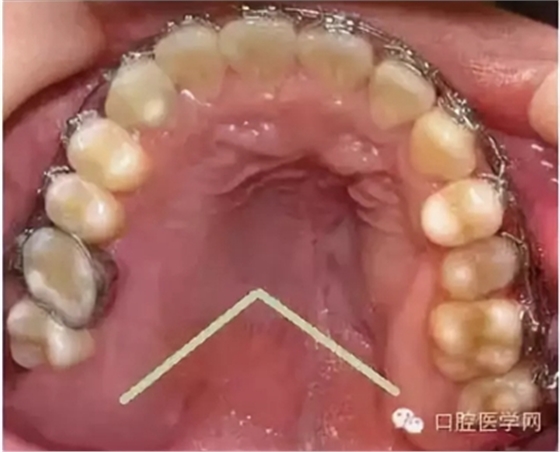

在臨床上我們需要把牙槽骨增生和骨隆突區(qū)分開來,骨隆突是在頜骨上的生理性骨性突起,并不是一個(gè)疾病癥狀,也不是疾病的表現(xiàn),比如舌側(cè)骨隆突、上頜骨骨隆突、下頜隆突是在第三磨牙和雙尖牙舌側(cè)的一個(gè)生理性突起。

2、對(duì)于生理性的骨隆突,一般也不進(jìn)行治療,在第三磨牙和雙尖牙舌側(cè)牙槽骨的舌側(cè)骨隆突、上頜骨骨隆突、下頜隆突等生理性突起,在進(jìn)行活動(dòng)義齒修復(fù)的時(shí)候應(yīng)該避讓開這些地方,以免義齒佩戴后產(chǎn)生壓痛。

5、牙槽骨修整術(shù)是一種牙槽外科常見手術(shù),其目的是去除妨礙義齒就位的影響如牙槽骨尖銳突起的骨嵴、突出的增生骨質(zhì)、上頜結(jié)節(jié)局部過于寬大肥厚的突起與倒凹,便于臨床義齒的修復(fù)治療。